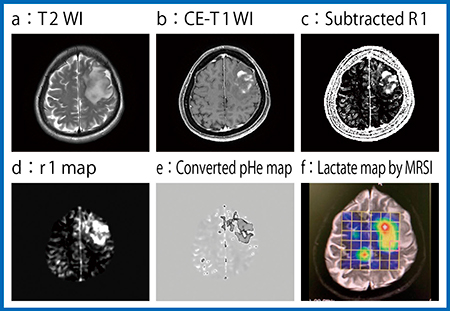

本症例は,造影前後のT1WIを見ても造影の有無が不明瞭であった。そこで,QPMを用いてR1(T1値の逆数)の造影前後のマップを差分したところ,辺縁の一部が白く描出され,内部に染み込むように部分的に厚くなっていることも認められた(図3 a〜c)。出血や石灰化があることで造影の有無がわかりにくいものの造影される腫瘍であると考えられ,鑑別を絞り込むことができた。さらに,MRSIでは,NAAは乏しく,乳酸が高い結果となった(図3 d)。以上の画像所見より術前診断は,脳室腫瘍として中心性神経細胞腫が疑われ,造影されなかった場合として類上衣腫が挙げられた。

図3 症例1の造影MRIとMRSI

この手法を用いて作成した退形成性神経膠腫症例のr1マップ(図8 d)と細胞外pHマップ(e)は,MRSIの乳酸マップ(f)と相関が認められた。